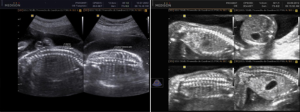

Ecografía Pélvica Ginecológica

Ecografía Pélvica Ginecológica Es un examen en el cual se introduce un transductor especial que será cubierto por un preservativo, a través de la vagina de